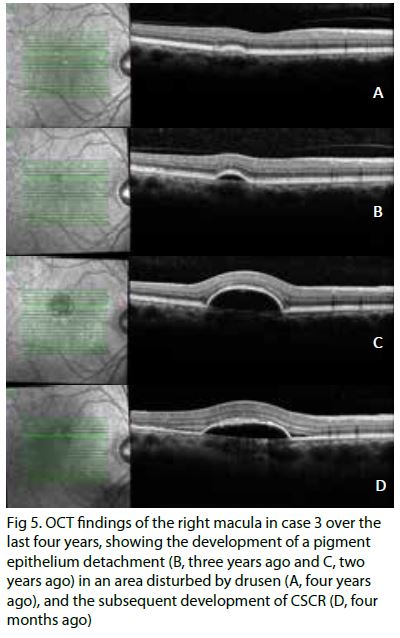

A 65-year-old man who’d noticed vision disturbance in his right eye for the past three months. Previously he had left CSCR which resolved after a prolonged period of observation. His acuity was 6/7.5 right and 6/6 left. Reviewing his previous imaging, there was choroidal thickening which gradually resulted in an enlarging pigment epithelium detachment (PED) in an area of the right macula with mild drusen. The large PED subsequently developed a microbreak with mild deflation, and surrounding fibrin and subretinal fluid when he became symptomatic (Fig 5).

Although there was an improvement in the amount of subretinal fluid three months after his right eye became symptomatic, there was still significant fibrin on the OCT imaging and a fluorescein angiogram showed an ongoing leak. Half-fluence PDT therapy was performed without any complications.